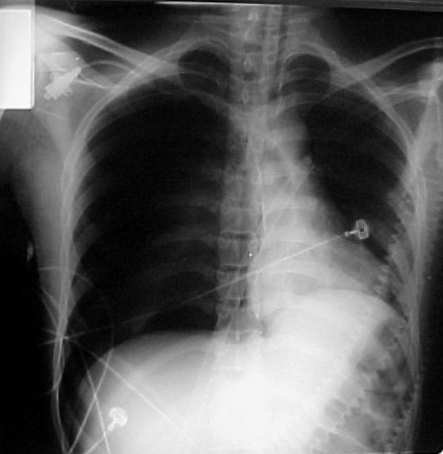

Chest X-Ray reveals hydropneumothorax on the left side